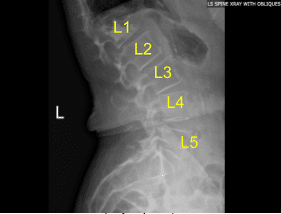

Postoperative Lumbar Spine X-ray Status Post Vertebroplasty of L1 Sagittal View

Approximately 5 cc of methyl methacrylate were injected overall with good height restoration and excellent placement across midline and creation of bony support with an L1 vertebral body proper. Once the methyl methacrylate had been injected and allowed to hardened to the desired consistency, the inner stylets of the Kyphon introducer nails were withdrawn and maintained in place for two minutes.

Final AP and lateral radiographs indicated excellent methyl methacrylate position with minimal to superior extravasation of the T12-L1 disk space. Accordingly the Kyphon one-touch introducer needles were withdrawn.

The patient initially followed up in one week after the surgery and then continued following up in our office 4, 6, and 8 weeks. In their last office visit they stated they were able to continue daily activities with little to no back pain. They also agreed to continue physical therapy.